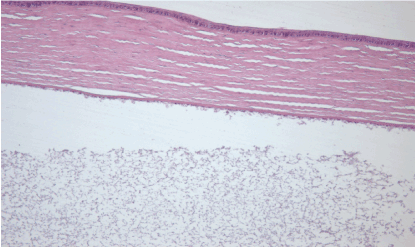

30th day – experimental group (A): the structural integrity of the cornea remained intact, loss in the cell density of the corneal endothelium. Hematoxylin and eosin dye, observed at 100x magnification. (Figure 21)

Figure 21. 30th day – experimental group (A).